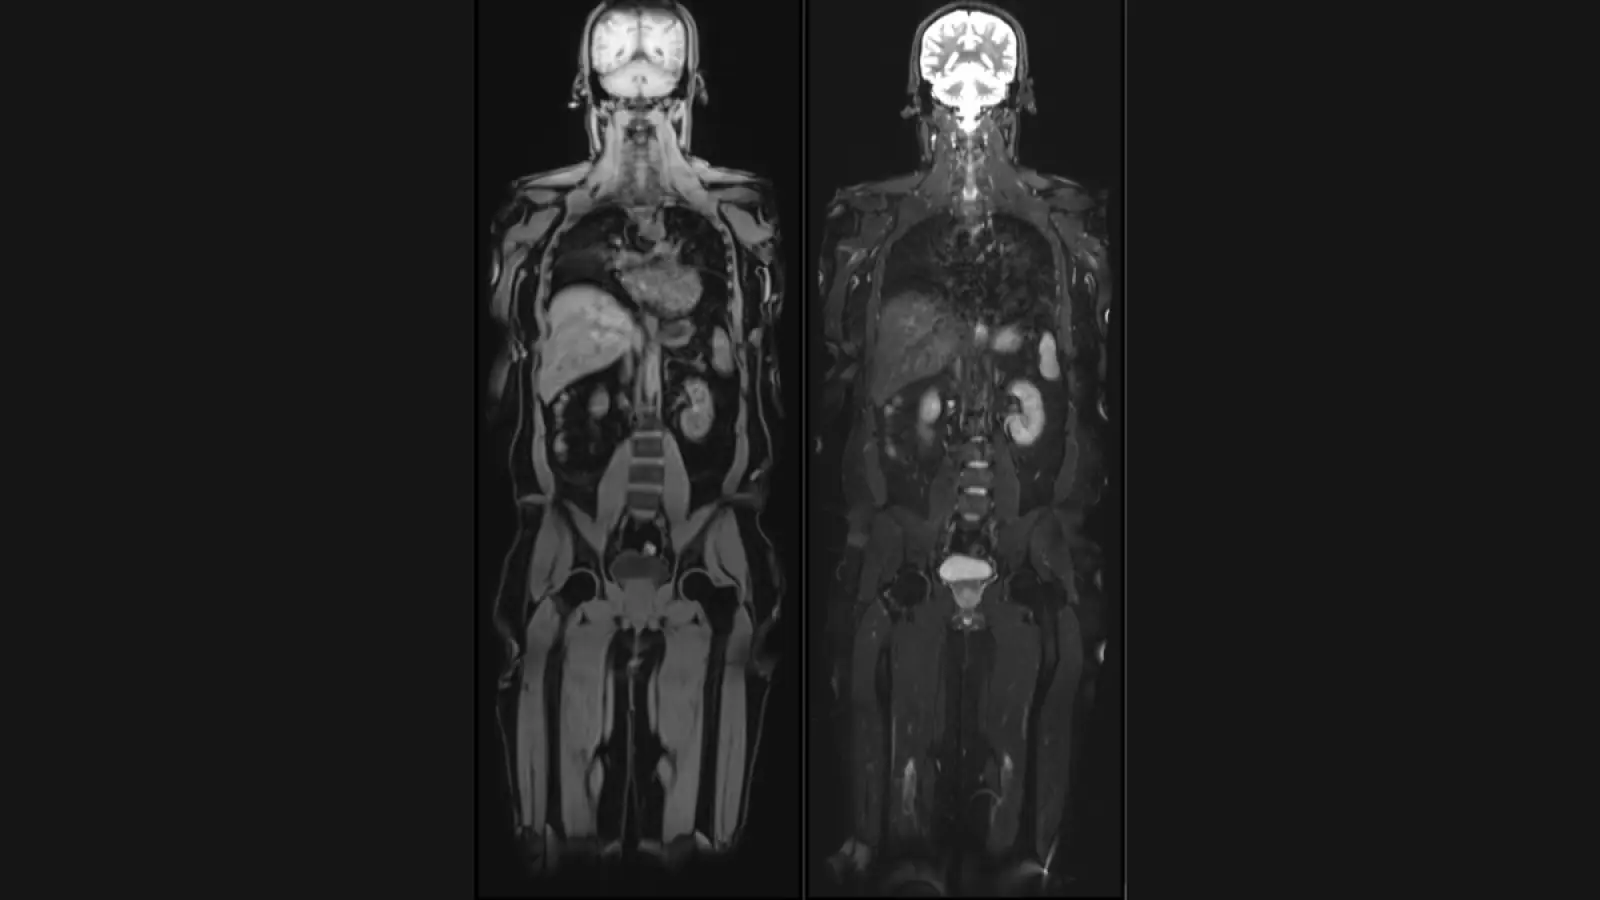

New Delhi [India], August 29: Aarthi Scans and Labs, a leading name in medical diagnostics, today announced the launch of its groundbreaking new unit, ‘Vital MRI.’ This innovative service offers comprehensive full body MRI scans at an affordable cost of ₹24,000, empowering individuals to take proactive steps towards their long-term health.

Vital Full Body MRI aims to detect potential health issues at their earliest stages, including early-stage cancers, aneurysms, spinal degeneration, disc bulges, and abnormalities in the brain, abdomen, and chest. The scans utilize cutting-edge technology to provide detailed, high-resolution images, enabling early diagnosis and intervention, thereby improving treatment outcomes.

Unique offerings of Vital MRI are – Brain volume analysis, Liver fat and Visceral fat quantification by MRI and Calcium scoring CT to assess heart attack risk. Brain volumetry analysis, generating a ‘Brain Age’ report that compares an individual’s brain health to their chronological age. This valuable insight can help individuals understand their cognitive well-being and take proactive measures to maintain brain health and prevent dementia.